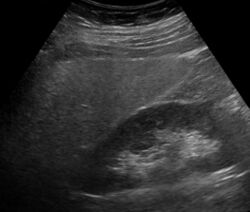

Ultrasound showing diffuse increased echogenicity of the liver

Imaging studies are often obtained during the evaluation process. Ultrasonography reveals a "bright" liver with increased echogenicity. Pocket-sized ultrasound devices might be used as point-of-care screening tools to diagnose liver steatosis. [30] [31] Medical imaging can aid in diagnosis of fatty liver; fatty livers have lower density than spleens on computed tomography (CT), and fat appears bright in T1-weighted magnetic resonance images (MRIs). Magnetic resonance elastography, a variant of magnetic resonance imaging, is investigated as a non-invasive method to diagnose fibrosis progression.[32] Histological diagnosis by liver biopsy is the most accurate measure of fibrosis and liver fat progression as of 2018.[8] Conventional imaging methods, such as ultrasound, CT and MRI, are not specific enough to detect fatty liver disease unless fat occupies at least 30% of the liver volume.[33]